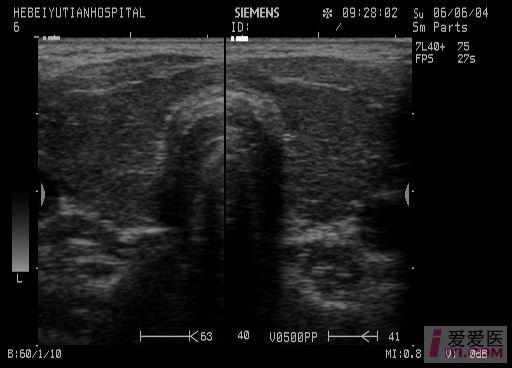

【讨论】甲减也能表现为"火海征"

当伴有甲亢时,血流信号较丰富,可有甲亢的火海征.

毒性弥漫性甲状腺肿内部血供丰富,呈"火海征",甲状腺上动脉流速>80cm